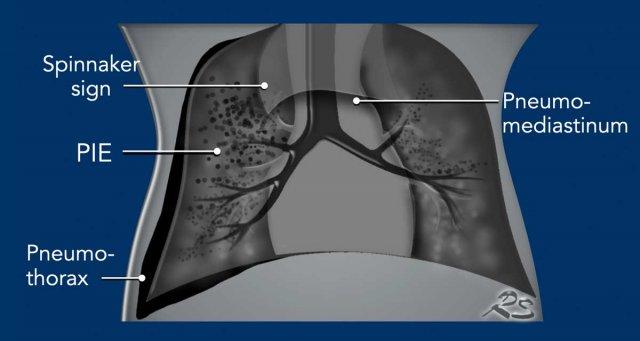

Rò khí do chấn thương áp lực ở trẻ sơ sinh biểu hiện như:

- Pneumothorax

- Pneumomediastinum and pericardium

- Pulmonary Interstitial Emphysema (PIE)

- Tracheal rupture

- Pneumatocele

Vỡ các đường dẫn khí tận cùng xảy ra do bơm áp lực cao vào mô phổi xẹp. Điều này gây ra rò rỉ khí vào mô kẽ phổi, hệ thống bạch huyết hoặc khoang màng phổi.

Một dấu hiệu đặc trưng trên phim ngực sơ sinh là rò rỉ khí lan dọc theo các phế quản được gọi là khí thũng mô kẽ phổi (PIE).

Khí trong mô kẽ có thể gây ra phổi cứng và kém đàn hồi, đồng thời làm giảm lưu lượng máu, dẫn đến giảm oxy hóa máu.

Tràn khí màng phổi có thể gây xẹp phổi, nhưng ở trẻ sơ sinh, phổi tương đối kém đàn hồi và mất thể tích thường bị hạn chế.

Khi có thêm tràn khí trung thất, có thể thấy hình ảnh ‘tuyến ức bị nâng lên’, còn được gọi là ‘Dấu hiệu Spinnaker’.

Pulmonary Interstitial Emphysema (PIE)

Khí thũng mô kẽ phổi (PIE) là tình trạng rò rỉ khí vào

các khoang quanh mạch máu và quanh phế quản do vỡ tại

các điểm nối phế quản-phế nang.

PIE được nhận biết dưới dạng các bóng khí nhỏ hoặc các tập hợp khí dạng tuyến tính

dọc theo bó mạch phế quản tỏa ra từ rốn phổi đến

ngoại vi.

PIE có thể xảy ra hai bên hoặc một bên.

Khi PIE đã hình thành, khí có thể lan theo hướng ly tâm dọc theo

các bao mạch phế quản hoặc các kênh bạch huyết để tạo thành các bóng khí dưới màng phổi, những bóng khí này

có thể vỡ vào khoang màng phổi và gây ra tràn khí màng phổi.